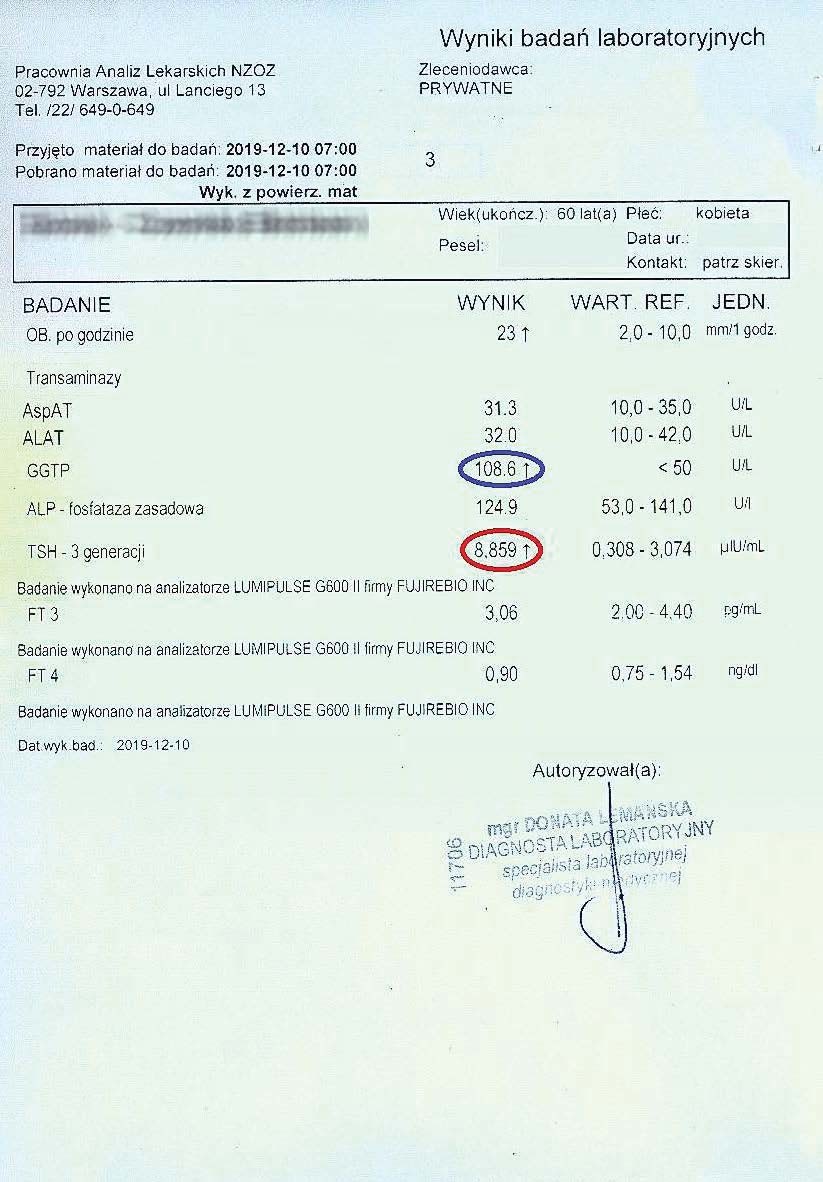

PRZYKŁAD EFEKTU PREPARATU NA NIEDOCZYNNOŚĆ TARCZYCY

Kobieta lat 59 z niedoczynnoscią tarczycy, bez przyjmowania lewotyroksyny. Kobieta przyjmowała preparat przez okres ponad 3 miesięcy. Przy zachowaniu naturalnego cyklu komórkowego i stałemu stymulowaniu mitochondriów osiągneła następujące wyniki kuracji:

Po zaobserwowaniu znacznej poprawy w ogólnym samopoczuciu, kobieta postanowiła wykonywać badania ze zwiększoną częstotliwością oraz kontrolę prób wątrobowych.

Po kolejnych dwóch miesiącach kobieta ponownie wykonała badania. Widoczne są: spadek TSH, obniżenie stanu zapalnego jak i spadek markeru wątrobowego GGTP.

Sukcesywnie co 2 miesiące można zaobserwować stały spadek parametrów zarówno wątroby jak i tarczycy. Kolejne badania potwierdzały dalszy spadek parametrów.

Po ponad roku kuracji badania wykazały dalszy postęp wycofania autoimmunologi tarczycy, potwierdzone również badaniem USG narządu.

Preparat wpływając na odbudowę mitochondriów zapewnił podłoże energetyczne do produkcji hormonów i odbudowy narządu. Brak ingerencji farmakologicznej wykazuje skuteczność nawet w podeszłym wieku, gdzie regeneracja jest wolniejsza a reakcje anaboliczne w znacznym stopniu spowolnione. Można zaobserwować także działanie ogólnoustrojowe obserwując spadek markeru wątroby, co jasno wykazuje poprawę funkcjonowania całego organizmu.